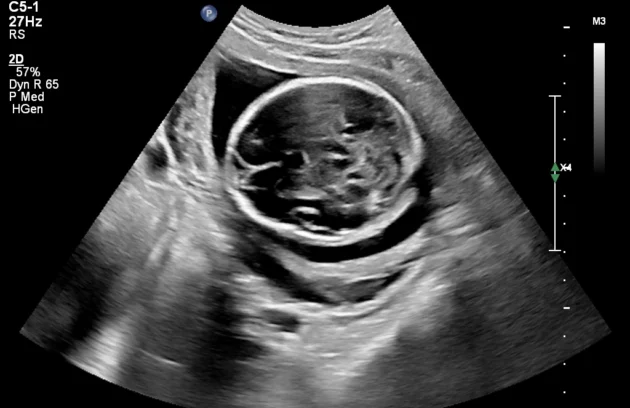

🔹 Anomaly Scan (Level II Ultrasound)

Anomaly Scan is a detailed ultrasound performed during pregnancy (usually between 18 and 22 weeks) to check the baby’s development. It helps detect structural abnormalities in the brain, heart, spine, kidneys, and other organs. This scan ensures your baby is growing normally and helps doctors identify any potential complications early. If you are looking for a reliable anomaly scan in Kathmandu, an early and accurate diagnosis is essential for a safe pregnancy.